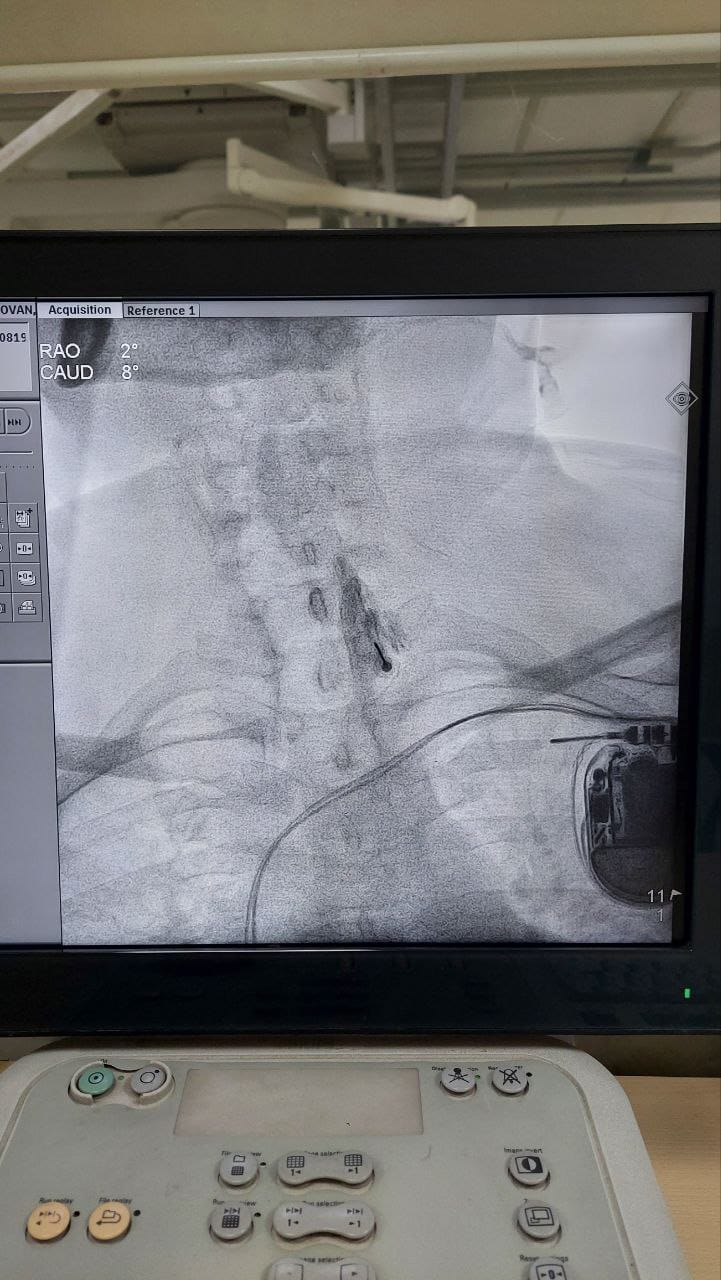

Struggling with chronic pain? Get advanced, personalised pain management from Dr. Manish De, one of Kolkata’s leading pain specialists. From knee pain, heel pain, low back pain, frozen shoulder, migraines, cancer pain to post-TKR persistent pain—Dr. De offers safe, evidence-based treatments across multiple locations: